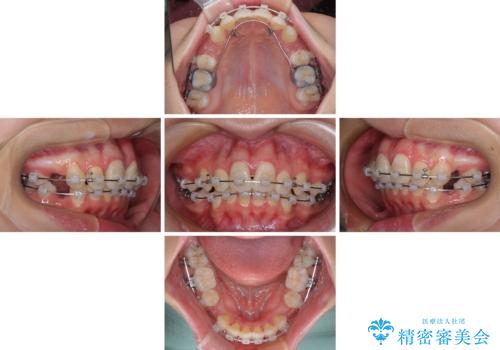

- クリアブラケット

下顎は叢生があったため、上下左右の第一小臼歯4本を抜歯し、更には口元の突出感を大きく改善させるために、上顎臼歯を後方に移動させるための補助装置をしようし、ワイヤー装置にて矯正治療を行うこととしました。

高校生ということもあり、治療期間は2年を切るスピードでした。